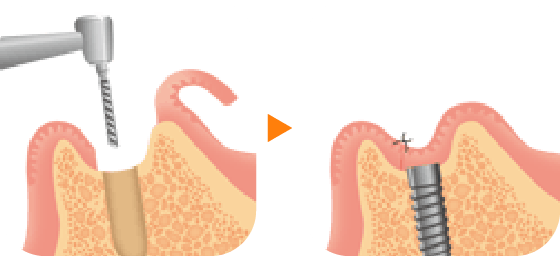

3 一次手術

(インプラント埋入)

アゴの骨にインプラント(人工歯根)を埋め込む手術を行います。局所麻酔を使用し、歯肉を切開して歯槽骨を露出させ、ドリルを使って孔を開け、インプラントを埋め込みます。最後に歯肉を縫い合わせます。経験豊富な歯科医師が担当しますので、インプラント1本あたり15分から20分程で手術は終わります。(骨移植など、骨造成を併用する場合はさらに時間を要します。)術後、2~3日程歯肉や頬が腫れる場合や、内出血がみられる場合があります。抗生剤と痛み止めを服用していただきます。